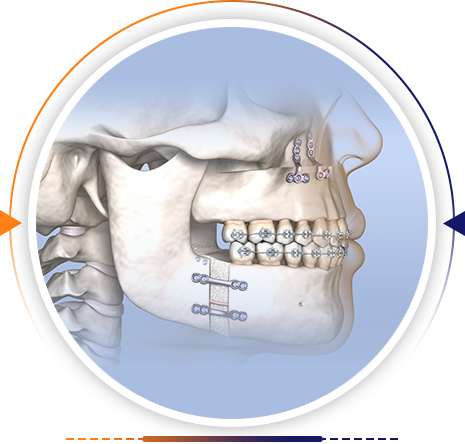

From ear, nose & throat problems to dental care, we provide complete solutions for the whole family. Expert care you can trust, all in one place

Consult our expert ENT doctor for accurate diagnosis and effective treatment.

- Sinus & Allergy Issues – Relief from chronic congestion and breathing difficulties.

- Hearing & Ear Infections – Comprehensive care for ear pain, infections, and hearing loss.

- Throat & Voice Disorders – Specialized treatment for sore throat, tonsils, and voice changes.

- Bleeding Gums — a common early sign of gum disease.

- Swelling or Redness — indicates infection or inflammation.

- Persistent Bad Breath — often linked to unhealthy gums.

- Receding Gums — can expose roots and cause sensitivity.

- Loose Teeth — advanced gum issues may lead to tooth loss.